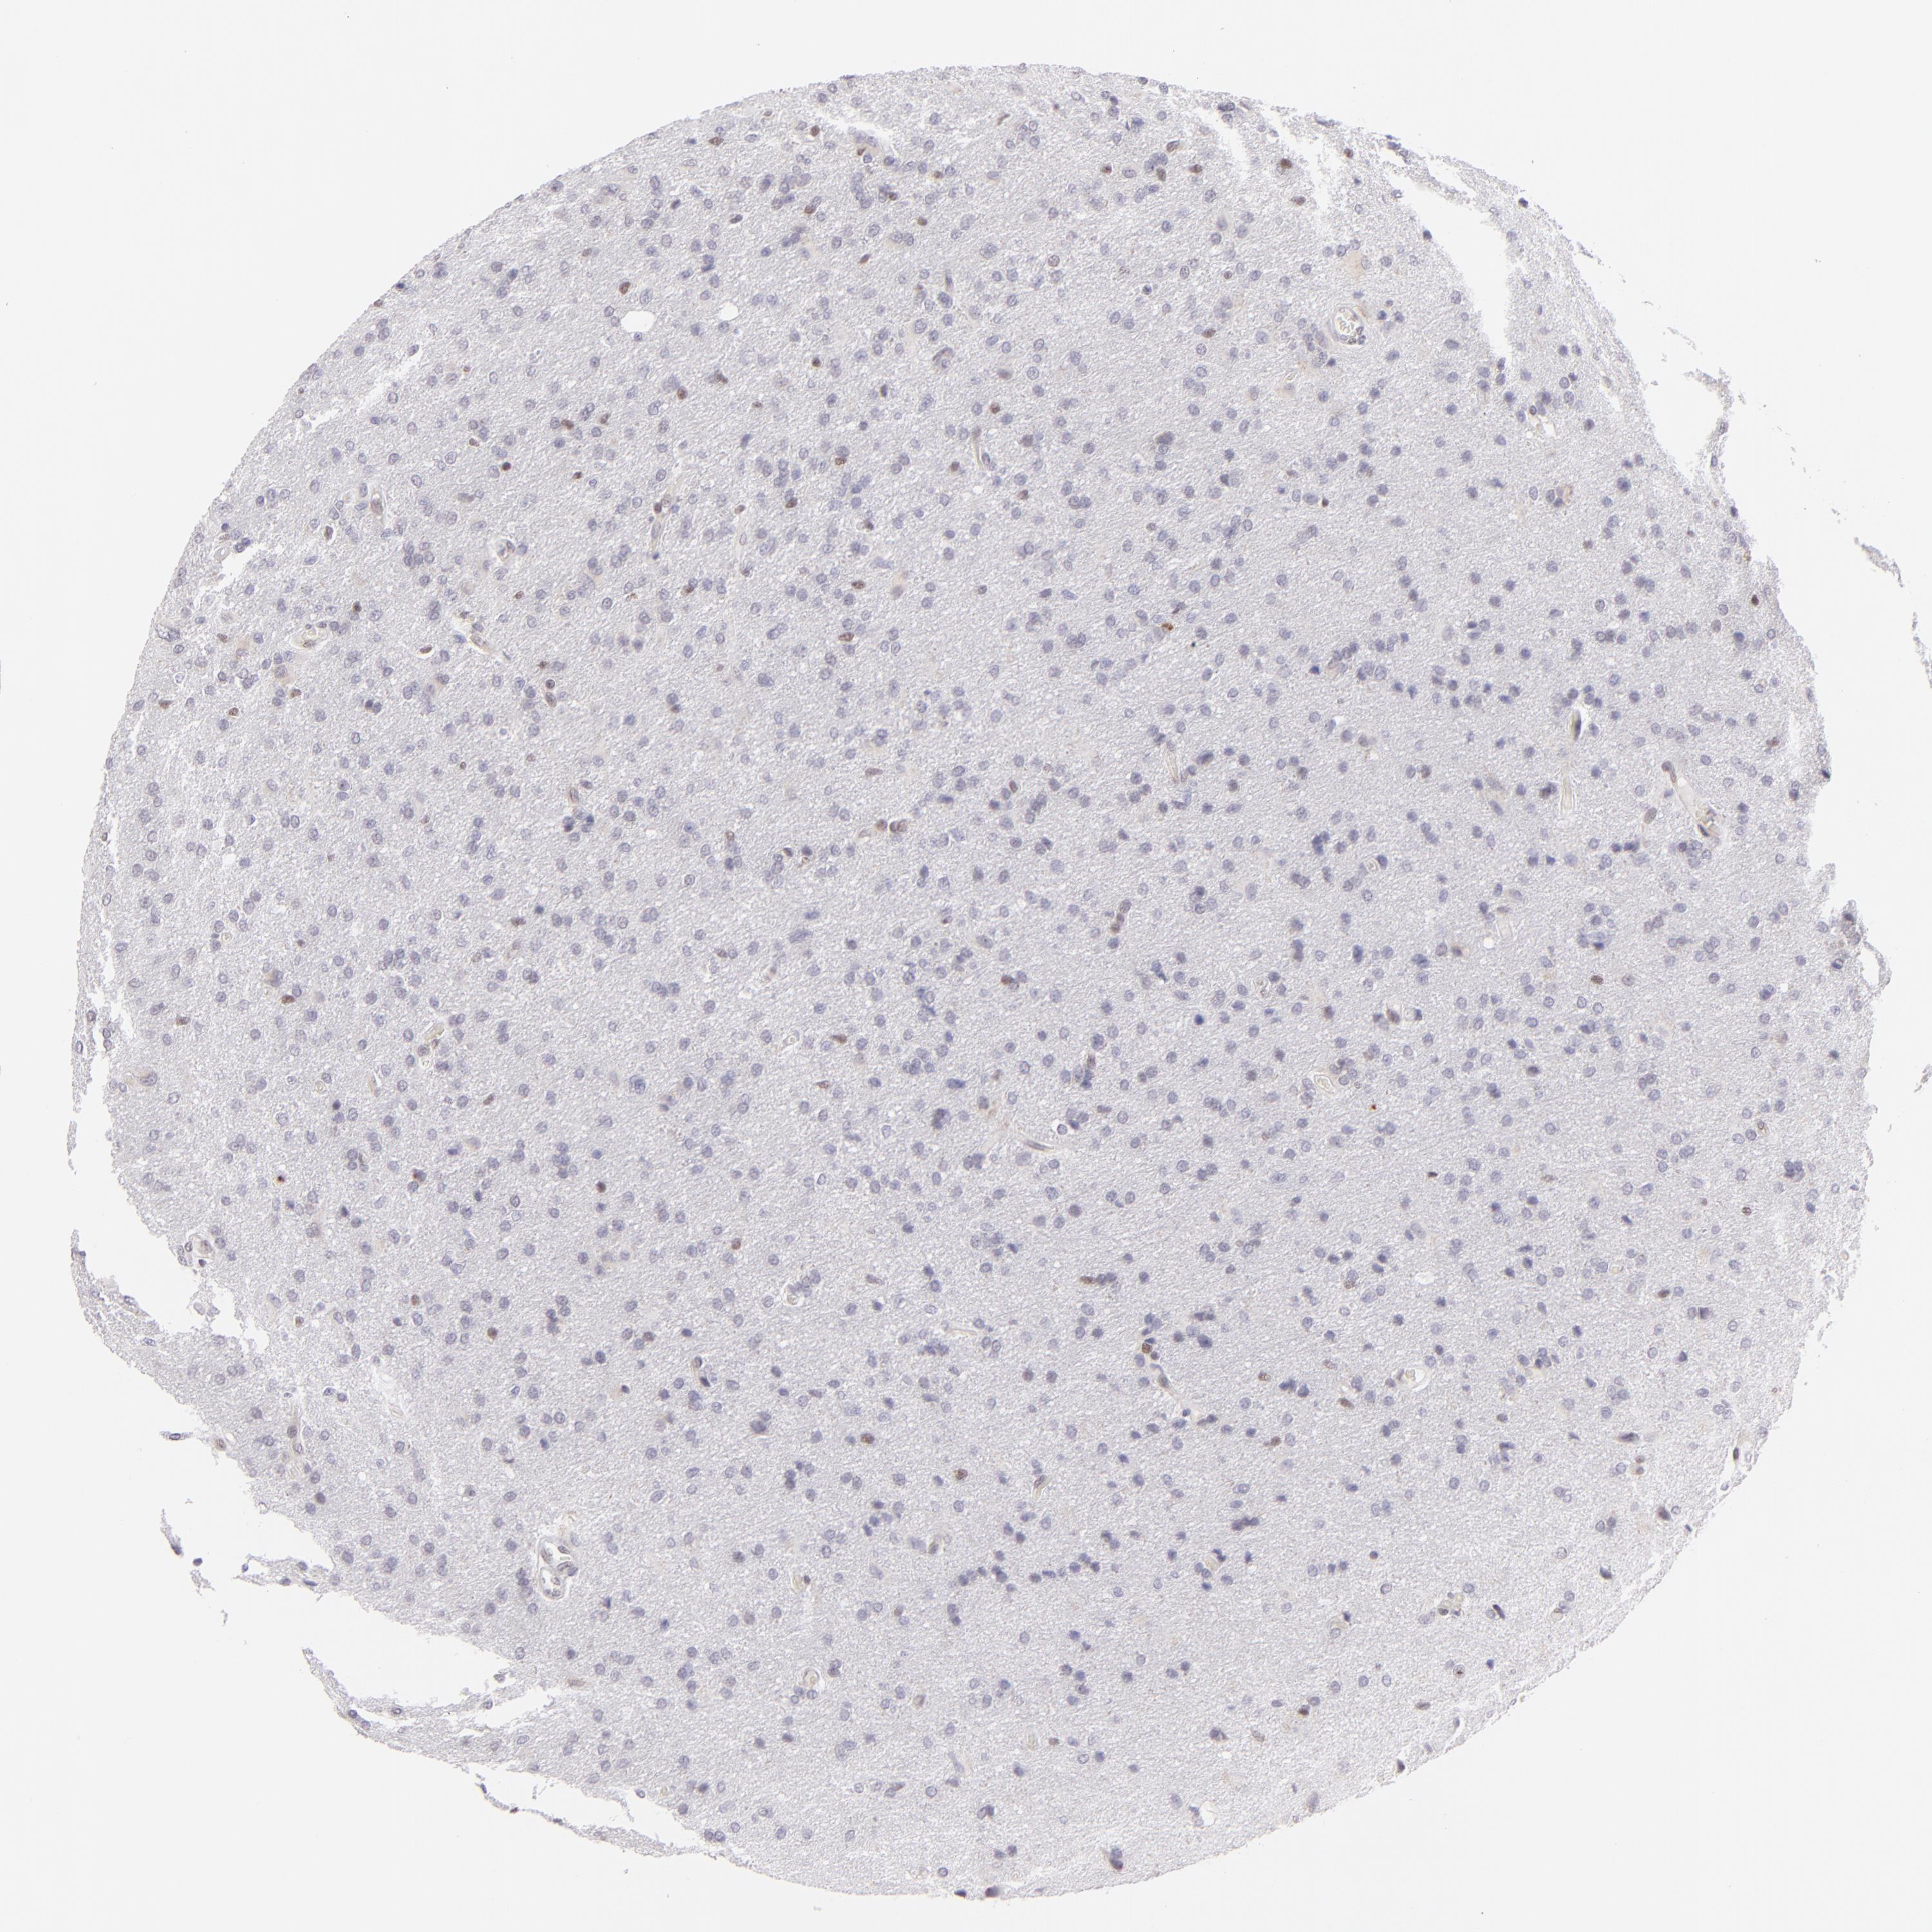

GLIOMA - Protein expressioni

A mouse-over function shows sample information and annotation data. Click on an image to view it in a full screen mode. Samples can be filtered based on level of antibody staining by selecting one or several of the following categories: high, medium, low and not detected. The assay and annotation is described here.

Note that samples used for immunohistochemistry by the Human Protein Atlas do not correspond to samples in the TCGA dataset.

Antibody stainingi

Antibody staining in the annotated cell types in the current human tissue is reported as not detected, low, medium, or high, based on conventional immunohistochemistry profiling in selected tissues. This score is based on the combination of the staining intensity and fraction of stained cells.

Each image is clickable and will lead to virtual microscopy that enables deeper exploration of all samples and also displays staining intensity scores, fraction scores and subcellular localization as well as patient and tissue information for each sample.

Antibody HPA064323

Antibody CAB002608

Glioma, malignant, Low grade

Glioma, malignant, High grade